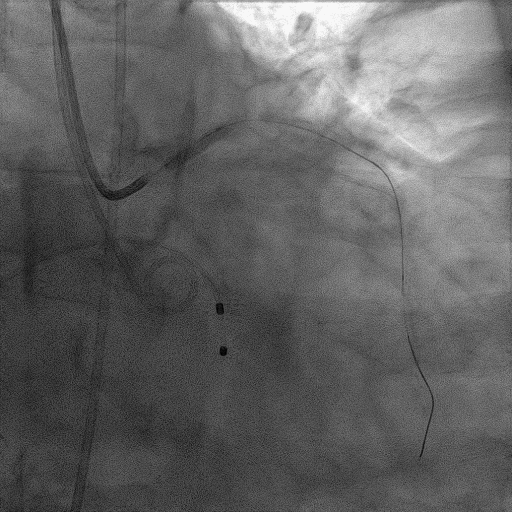

CAG:LAD近中段弥漫钙化,近段80%狭窄,中段90%狭窄,D190%狭窄,中间支近段90%狭窄,右冠近中段弥漫病变,最重狭窄50%。考虑患者胸痛症状可能为冠心病+AS共同作用,以及患者冠脉病变钙化严重,予以旋磨+PCI+TAVR一站式处理。

于中间支植入2.5*18mm支架

1.5mm旋磨头以16万RPM旋磨三次

3.0*15mm球囊后扩张

3.0*15mm球囊预处理LAD近段病变

复查冠脉造影结果满意